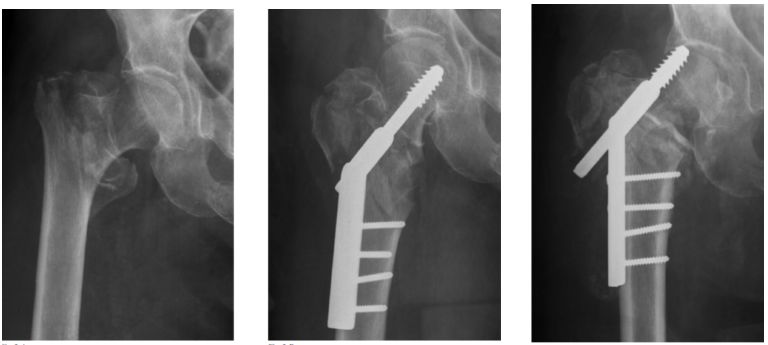

DHS(Dynamic Hip Screw)动力髋螺钉

以一根粗大宽螺纹的拉力螺钉与套管钢板及加压螺钉连接。在复位及骨折愈合过程中可使两骨折端靠拢,产生静力加压作用。对于顺转子间骨折线骨折可获得动力加压作用。

稳定骨折,固定成功

不稳定骨折,固定失败

对于不稳定骨折,髓内固定的力学性能更好,力臂更短,术后器械相关并发症如股骨头切割、髋内翻、短缩和内固定物松动断裂概率更低。

PFNA(股骨近端螺旋刀片抗旋髓内钉proximal femoral nail anti-rotation blade)